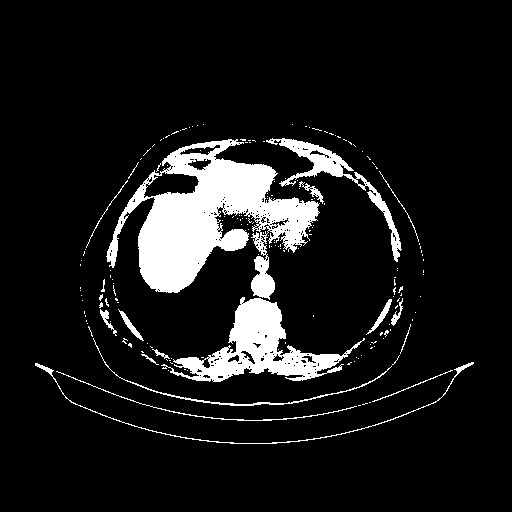

Generated VENOUS CT scan (A→B translation)

Full window (WL 1023.5, WW 4095 β†’ Low βˆ’1024, High +3071)

Actual HU range: [-1024.0, 3071.0]